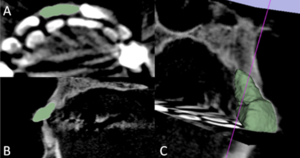

Computed Tomographic Evaluation of Cleft Palate in One-day-old Puppies

Publication: BMC Vet Res. 2018 Oct 20;14(1):316. PMID: 30342508 | PDF Authors: Pankowski F, Paśko S, Max A, Szal B, Dzierzęcka M, Gruszczyńska J, Szaro P, Gołębiowski M, Bartyzel BJ. Institution: Department of Morphological Sciences, Faculty of Veterinary Medicine, Warsaw University of Life Sciences - SGGW, Warsaw, Poland. Abstract: BACKGROUND: Cleft palate is a birth defect characterized by a lack of fusion between structures forming the palate. Causes include a multitude of factors, both genetic and environmental. Computed tomography (CT) is widely used to evaluate morphological features and diagnose head disorders in adult dogs. However, there is less data about its use in neonatal dogs. The purpose of this study was to perform CT evaluation of palatal defects in one-day-old puppies and to present a novel approach of 3D modeling in terms of cleft palate assessment. RESULTS: Macroscopic and CT examinations were performed in 23 stillborn or euthanized purebred newborn puppies. On the basis of CT data, a 3D model was prepared and the cleft surface area was then calculated. A multi-stage approach, which utilised software such as 3D Slicer and Blender, was applied. Palatal defects were found in ten dogs, of which five had cleft palate, three had bilateral cleft lip and palate, one had a unilateral cleft lip and palate and one had a unilateral cleft lip. The surface area of the clefts ranged from 31 to 213 mm2, which made up respectfully 11 to 63% of the total surface area of the palate. No abnormalities were found in thirteen dogs and they made up the control group. CONCLUSIONS: Computed tomography and 3D modeling were very effective in evaluation of palatal disorders in newborn dogs. 3D models adapted to the natural curvature of the palate were created and more precise data was obtained. Morphological characteristics, CT findings and advanced image analysis of cleft palate in neonates obtained from these models increase the knowledge about this malformation in dogs. |